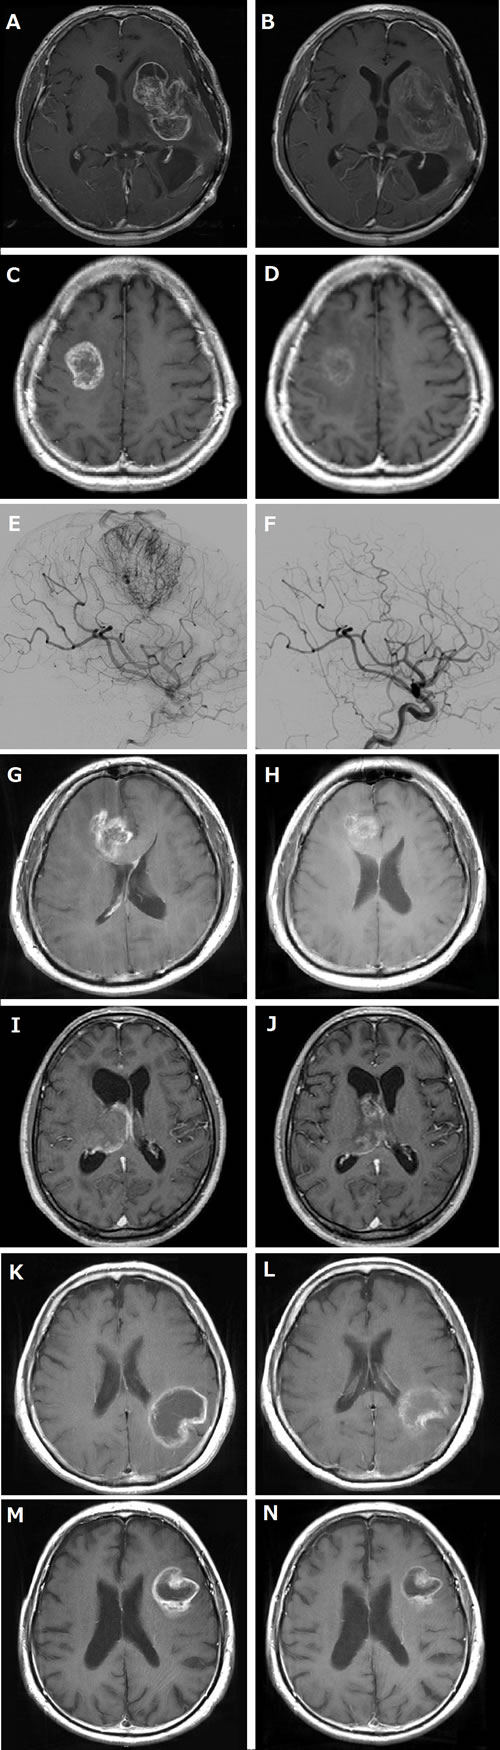

A 48-year-old Asian man presented with tumor regrowth (1st recurrence) after the initial chemoradiotherapy for left temporal anaplastic astrocytoma. A subtotal removal of the recurrent tumor was performed (2nd surgery), and the histopathological diagnosis was glioblastoma. Complete response was obtained by postoperative temozolomide; however, tumor recurrence was noted 8 months following surgery (2nd recurrence), and the patient was then treated with Bev. After the 1st course of Bev (10 mg/kg), although the tumor bulk remained stable, contrast enhancement almost disappeared, and the surrounding high-intensity area on T2/fluid-attenuated inversion recovery images reflecting peritumoral edema improved (RANO: SD, change in sum of the products of the perpendicular diameter (SPD) estimated by T1 weighted images with contrast enhancement: −8%) (Figure 1A and 1B).[10] Because of persistent headache and patient’s hope for mass reduction, tumor removal after neoadjuvant Bev was planned and performed on day 36 of the 3rd course of Bev (continued effect of Bev was confirmed on MRI a day before operation, 3rd surgery). Intraoperatively, the tumor was milky-whitish; a quite different appearance as compared with the grayish to brownish previous tumor (Figure 2). Distinctiveness of the tumor margin was similar to that of the previous surgery with margins being mostly clear, although not clear at some deep parts. The tumor appeared hypovascular, and there was no particular difficulty in hemostasis. Because of lateral striate arteries penetrating the tumor, partial removal was performed (about 70%). BCNU wafer was placed on the resection margins. Suture removal was uneventfully done on day 30 after operation.

A 49-year-old Asian man presented with an extremely hypervascular tumor in the right premotor area that was suspicious of glioblastoma (Figure 1C and 1E). Therefore, to decrease blood loss during surgery and to facilitate safe resection, tumor removal was planned after neoadjuvant Bev therapy. After two courses of Bev (10 mg/kg, day 0, 15) and one course of temozolomide (150 mg/m2, days 1-5), tumor volume was decreased, and angiography showed a disappearance of tumor stain (RANO: PR, SPD change: −52%) (Figure 1D and 1F). On day 21 of the 2nd course of Bev, gross total tumor removal was performed. Intraoperatively, the tumor was mostly yellowish, suggestive of necrosis. Tumor margins were mostly distinguished from the surrounding parenchyma. The tumor appeared hypovascular, and there was no difficulty in hemostasis. Suture removal was uneventfully done on day 12 after operation.

A 55-year-old Asian man presented with a ring-enhanced lesion mainly located in the right frontal lobe with severe perifocal edema, and glioblastoma was suspected. To possibly decrease the extent of tumor and to facilitate operative radicality, tumor removal was planned after neoadjuvant Bev therapy. MRI after one course of Bev (10 mg/kg) revealed the marked improvement of the abnormal enhancement of the tumor as well as perifocal edema (RANO: PR, SPD change: -61%) (Figure 1G and 1H). On day 21 of the 1st course of Bev, gross total tumor removal was performed. Intraoperatively, the tumor presented as yellowish. Although the tumor was hypovascular, tumor margins were not very clear at most parts. There was no difficulty in hemostasis. Protoporphyrin IX fluorescence after the administration of 5-aminolevlinic acid was identified. Although there was a subcutaneous retention of the cerebrospinal fluid postoperatively, it gradually recovered. Suture removal was uneventfully done on day 14 after the operation.

A 68-year-old Asian man presented with headache and disorientation. MRI showed irregularly enhanced lesion in the right thalamus with severe perifocal edema and hydrocephalus, and glioblastoma was suspected. Although the patient was initially conscious, he progressed rapidly to a state of drowsiness. Therefore, there was an urgent need to decrease tumor volume; hence, Bev was administered. After one course of Bev (10 mg/kg), MRI showed an improvement of perifocal edema and hydrocepharus as well as decrease of abnormal enhancement of the tumor (RANO: SD, SPD change: −23%) followed by improvement in consciousness (Figure 1I and 1J). On day 15 of the 1st course of Bev, endoscopic biopsy was performed. There was no difficulty in intraoperative hemostasis. Suture removal was uneventfully done on day 7 after operation.

A right-handed, 77-year-old Asian female presented with a ring-enhanced lesion mainly located in the left parietal lobe, and glioblastoma was suspected. To possibly decrease the extent of the tumor located in the eloquent area and to minimize the post-operative complication, tumor removal was planned after neoadjuvant Bev therapy. MRI after one course of Bev (10 mg/kg) revealed the improvement of the abnormal enhancement of the tumor as well as perifocal edema (RANO: SD, SPD change: -14%) (Figure 1K and 1L). On day 26 of the 1st course of Bev, gross total tumor removal was performed. Intraoperatively, the tumor presented as brownish. Although the tumor was hypovascular, tumor margins were not very clear at most parts. There was no difficulty in hemostasis. Protoporphyrin IX fluorescence after the administration of 5-aminolevlinic acid was identified. Suture removal was uneventfully done on day 14 after the operation.

A right-handed, 83-year-old Asian man presented with a ring-enhanced lesion in the left frontal lobe, and glioblastoma was suspected. To possibly decrease the extent of the tumor located in the language area and to minimize the post-operative complication, tumor removal was planned after neoadjuvant Bev therapy. MRI after one course of Bev (10 mg/kg) revealed the improvement of the abnormal enhancement of the tumor as well as perifocal edema (RANO: SD, SPD change: -43%) (Figure 1M and 1N). On day 27 of the 1st course of Bev, gross total tumor removal was performed. Intraoperatively, the tumor presented as dull red. Although the tumor was hypovascular, tumor margins were not very clear at most parts. There was no difficulty in hemostasis. Protoporphyrin IX fluorescence after the administration of 5-aminolevlinic acid was identified. Suture removal was uneventfully done on day 14 after the operation.

Figure 1: MRI and angiography of before and after neoadjuvant bevacizumab (Bev). A-D, G-N,: T1-weighted images with contrast enhancement, E and F: cerebral angiography. A, C, E, G, I, K and M: before Bev treatment. B, D, F, H,J, L and N: after Bev treatment (before removal). A. and B. Showing decrease of contrast enhancement and disappearance of peritumoral edema by three courses of neoadjuvant Bev in case 1. Change in sum of the products of the greatest perpendicular diameter (SPD) was −8%. C. and D. Showing volume decrease and improvement of contrast enhancement of the right premotor tumor in case 2 by two courses of neoadjuvant Bev and one course of temozolomide. SPD change was −52%. E. and F. Note that the prominent tumor staining in case 2 was disappeared by two courses of neoadjuvant Bev and one course of temozolomide. G. and H. Showing volume decrease and marked improvement of contrast enhancement as well as peritumoral edema of the right frontal-corpus callosum tumor in case 3 by one course of neoadjuvant Bev. SPD change was −61%. I. and J. Showing mild tumor volume decrease and improvement of contrast enhancement as well as hydrocepharus in case 4 by one course of neoadjuvant Bev. SPD change was −23%. K. and L. Showing volume decrease and marked improvement of contrast enhancement as well as peritumoral edema of the left parietal lobe tumor in case 5 by one course of neoadjuvant Bev. SPD change was −14%. M. and N. Showing volume decrease and marked improvement of contrast enhancement as well as peritumoral edema of the left frontal lobe tumor in case 6 by one course of neoadjuvant Bev. SPD change was −43%.